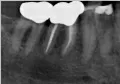

Здравствуйте! Есть ли у меня киста? Если да, то как срочно нужно делать операцию и как она называется?

Какой зуб вы имеете ввиду? Уточните. 18 и 48 зуб необходимо удалить. Далее расскажу после уточнения.